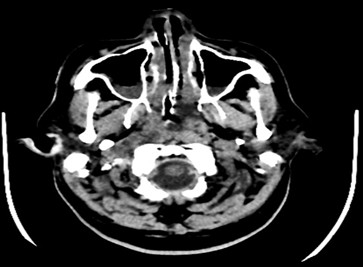

Hypoglycemia was managed with intravenous 25% dextrose and insulin infusion, with blood sugar monitored regularly and diabetes managed according to blood sugar levels. Routine laboratory investigations revealed elevated total leukocyte count, increased C‑reactive protein, and elevated procalcitonin levels, suggestive of systemic infection or inflammatory response. Neurological evaluation was undertaken, and neurologist opinion was obtained. Electroencephalography (EEG) showed intermittent polyspike, wave discharge noted and posterior predominant alpha rhythm. CT brain, and MRI brain were performed, which demonstrated diffuse cerebral edema. Neurologist’s advice was followed. The patient was treated with intravenous antibiotics, anticonvulsants, intravenous fluids (5% dextrose), anticoagulants, antiplatelets, osmotic diuretics, anti‑inflammatory drugs, vitamin supplements, proton pump inhibitors, nebulisation, and other supportive care measures.

Fig (1): CT brain plain